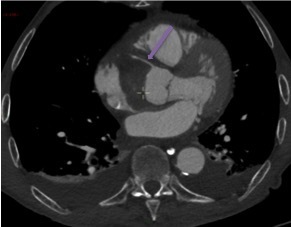

Un angioscanner thoraco-abdomino-pelvien est donc réalisé. Les Figures 11, 12, 13, 14 et 15 présentent des reformations axiales issues de celui-ci.

Question 7 : Concernant les structures légendées, quelles sont la/les proposition(s) exacte(s) ?

Vrai chenal

Déchirure intimale, qui constitue la porte d’entrée de la dissection.

Artère carotide commune droite

Artère coronaire droite naissant du sinus de Vasalva

Visualisation de la déchirure intimale d’où nait le faux chenal, dans lequel la déchirure est éversée, au niveau de l’aorte ascendante, avec un flap intimal étendu au tronc artériel brachio-céphalique, à la carotide commune droite et à la carotide commune gauche. En revanche absence d’extension au sinus de Vasalva, à la coronaire droite.

Dissection aortique de type A selon Stanford avec porte d’entrée de l’aorte ascendante en amont du tronc artériel brachio-céphalique et extension aux troncs artériels supra-aortiques. Pas d’extension au sinus de Vasalva, aux coronaires ni à l’aorte descendante. Pas de signe de rupture intra-péricardique ou intra-médiastinale.